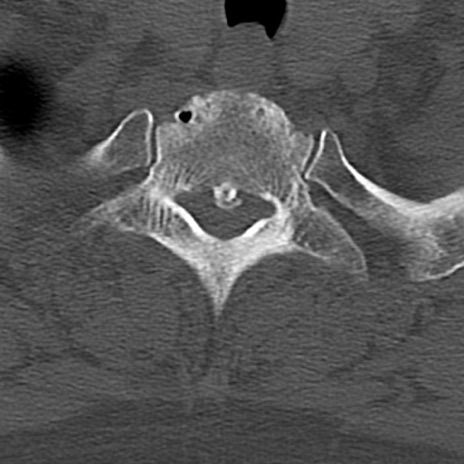

頚椎CT

横断像